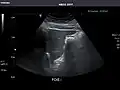

Renal ultrasonography

Ultrasound scan of a kidney (right side)

Ultrasonography of the kidneys is essential in the diagnosis and management of kidney-related diseases. The kidneys are easily examined, and most pathological changes in the kidneys are distinguishable with ultrasound.[7]

Kidneys: Right and left kidneys measure 11.5 cm and 12 cm in length respectively. No hydronephrosis. Small left lower pole kidney cyst.